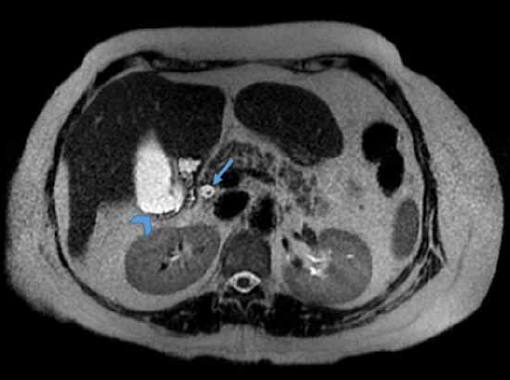

Paciente del sexo femenino de 58 años que acudió al servicio de urgencias por presenar un cuadro de dolor abdominal localizado en el epigastrio, transfictivo. Los estudios de laboratorio mostraron elevación de bilirrubinas a expensas de la bilirrubina directa.

Figura 1 Colangio resonancia; muestra la vía biliar intra y extrahepática, donde existe ausencia de señal en la desembocadura del colédoco así como en zonas del interior de la vesícula biliar.